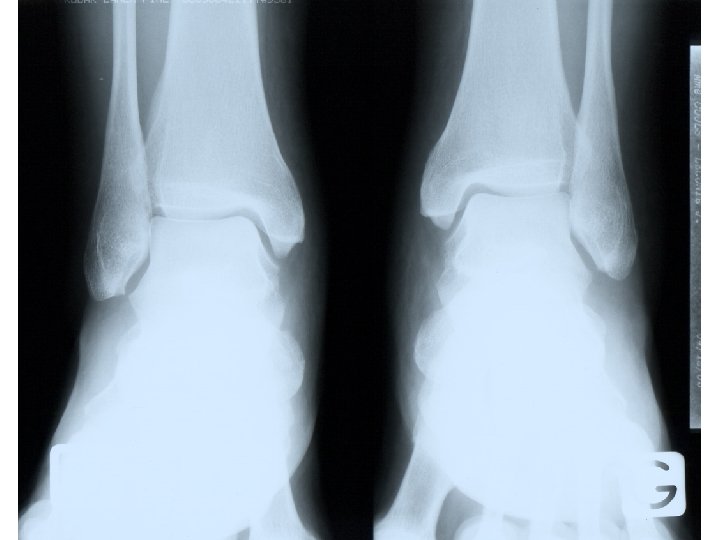

Une femme de 40 ans décrit des douleurs des chevilles apparues en décembre 2009, insuffisamment soulagées par la prise d’antalgiques mais répondant bien aux AINS. ATCD : HTA traitée par Avlocardyl, une grossesse, pas d’antécédent de faussecouche, pas d’antécédent thromboembolique. Vous la voyez pour la 1ère fois début février 2010 car sont apparues secondairement des douleurs très invalidantes du genou gauche, du poignet droit et du coude droit. L’examen clinique montre encore un empâtement des chevilles, révèle des douleurs à la pression du poignet droit et réveille des douleurs du coude droit à la mobilisation. L’auscultation cardio-pulmonaire est par ailleurs normale, la pression artérielle est à 11/6, le poids est à 71 kg pour 1 m 65. Vous réalisez des radiographies standard : chevilles, genoux, mains et poignets qui sont sensiblement normales ainsi qu’un bilan biologique: hémoglobine : 13, 8 g/d. L, globules blancs 5 400/mm 3, plaquettes 195 000/mm 3, VS : 8 mm/h, CRP : 3 mg/L.

Atteinte rénale: Classification de l’OMS Classe I : glomérules optiquement normaux (dépôts mésangiaux d’Ig en IF) Classe II : atteinte mésangiale avec épaississement et prolifération cellulaire ; IF positive Classe III : glomérulonéphrite segmentaire et focale : prolifération endo- et/ou extracapillaire avec moins de 50% des glomérules touchés Classe IV : glomérulonéphrite proliférative diffuse : atteinte endo- et parfois extracapillaire avec atteinte de plus de 50 % des glomérules Classe V : glomérulonéphrite extramembraneuse Classe VI : glomérulonéphrite avec sclérose évoluée